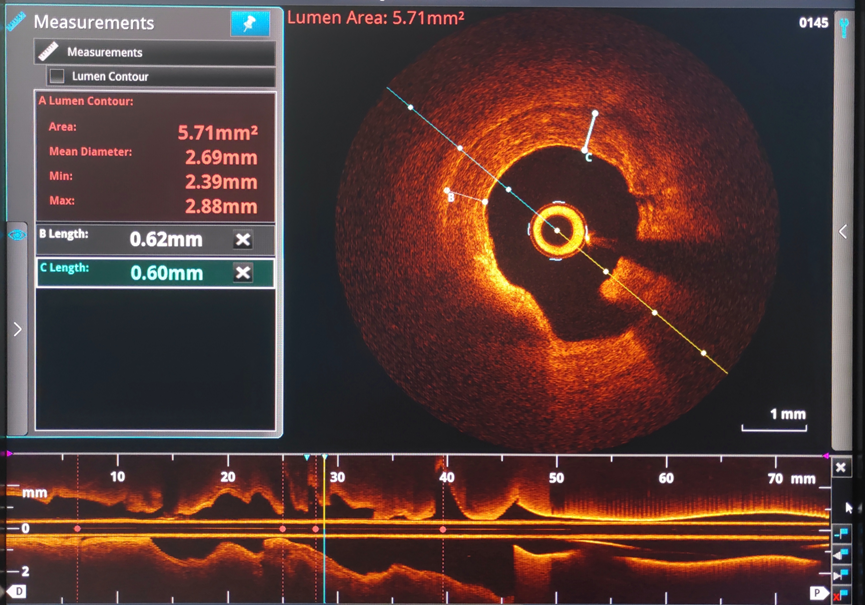

经过充分的术前准备,术前OCT检查提示:前降近中段钙化病变处可见90-360°环形钙化,钙化厚度约0.38mm-0.6mm,长度约10mm,局部可见钙化小结。较厚的环形钙化是导致上次手术使用高压球囊及切割球囊无法顺利打开病变的原因。针对病变特点,在OCT的精确定位下,启用3.5x12mm Shockwave冲击波球囊技术在环形钙化处精准震荡扩张,启动脉冲发生器,持续激发脉冲10S,可见球囊逐渐膨胀充分,随后以6atm扩张震波球囊,可见球囊扩张满意。重新定位冲击波球囊,重复脉冲3个周期共4个周期脉冲优化震波碎裂疗效,复查OCT清楚可见环形钙化斑块碎裂松解,局部未见明显夹层,获得较大管腔,满足支架植入条件。成功于左前降支近段植入3.5mm*13mm药物洗脱支架1枚。

Shockwave球囊治疗前后OCT成像对比:

Shockwave球囊治疗前

Shockwave球囊治疗后